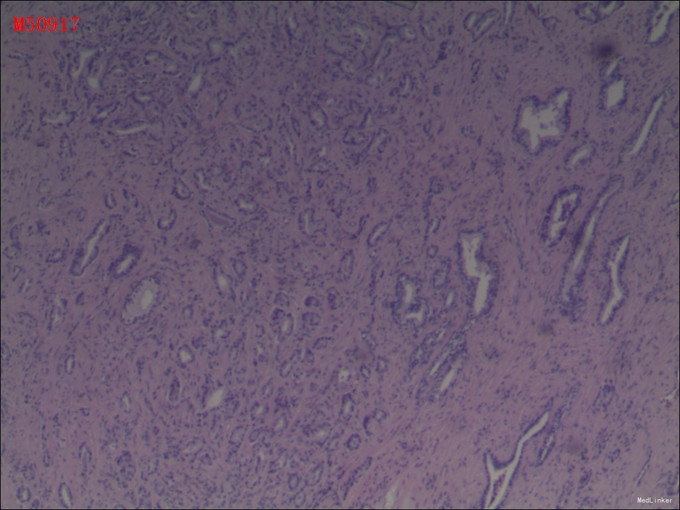

病理:1(前列腺及精囊腺)送检5x4x4cm前列腺一个,左侧精囊腺4x2x0.5cm,输精管长5cm,右侧同左侧。镜下:前列腺腺癌,Gleason评分3+3=6分。双侧输精管及精囊腺未见癌。2(膀胱颈切缘组织)送检直径0.5cm组织一块,全埋制片。镜下:膀胱壁组织,未见癌。3(右侧部分精囊腺)送检直径1cm组织一块,切开全埋制片。镜下:右侧精囊腺组织,未见癌。